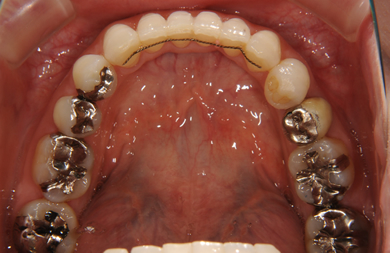

矯正の症例写真 ORTHODONT

全顎矯正治療

| 性別/年齢 | 女性 / 31歳 | ||||||||||||||||||||||||||||||||

| 主訴 | 歯並びを綺麗にしたい。 | ||||||||||||||||||||||||||||||||

| 治療方針 | 口元がきれいなので、なるべく横顔を変えないように歯を抜かずに治療を行う。しかし、下顎がだいぶ前に出ていて、上下の顎の前後的な位置のずれが大きいため、下顎にはインプラントアンカーを用いて、下の歯を本来の位置まで後ろに引っ張って治す。 | ||||||||||||||||||||||||||||||||

| 治療内容 | 唇側矯正(シルバー)、保定装置、矯正用スピードインプラント2本 | ||||||||||||||||||||||||||||||||

| 総治療費 | 634,000円 | ||||||||||||||||||||||||||||||||

| 治療期間 | 1年5ヶ月 |